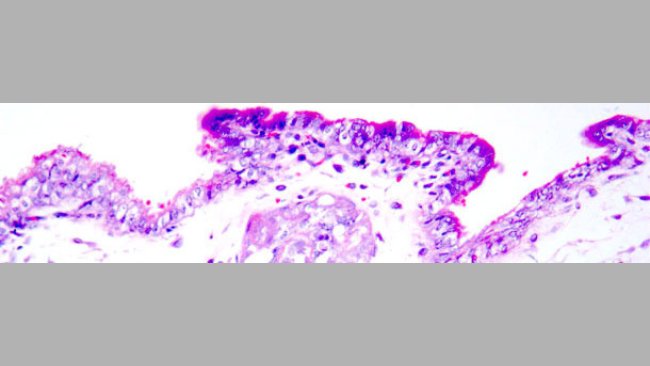

La vaccinazione delle scrofette contro il PCV2, prima dell'inseminazione con seme infetto da PCV2, ha diminuito chiaramente la carica e l'escrezione virale, fino a valori compatibili con la protezione dei feti.